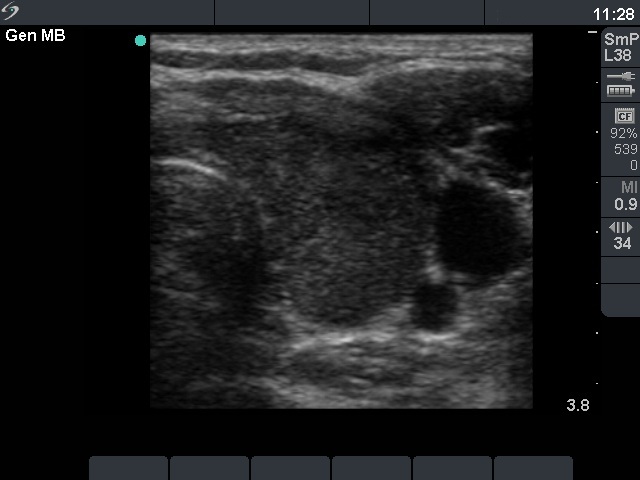

First examination (first and second row of images):

Clinical presentation: A 33-year-old woman was referred with typical complaints of subacute thyroiditis lasting for 6 weeks.

Palpation: Both lobes were hard and painful.

Functional state: moderate degree of hyperthyroidism with TSH-level 0.001 mIU/L, FT4 27.2 pM/L. Erythrocyte sedimentation rate was 49 mm/H, CRP was 9.2 mg/L.

Ultrasonography: The thyroid was hypoechogenic and inhomogeneous. The vascularization was average.

Cytological diagnosis: subacute, granulomatous de Quervain's thyroiditis.

Suggestion: steroid therapy for 6 weeks.